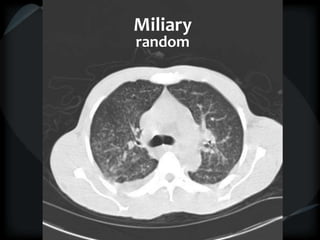

miliary

random